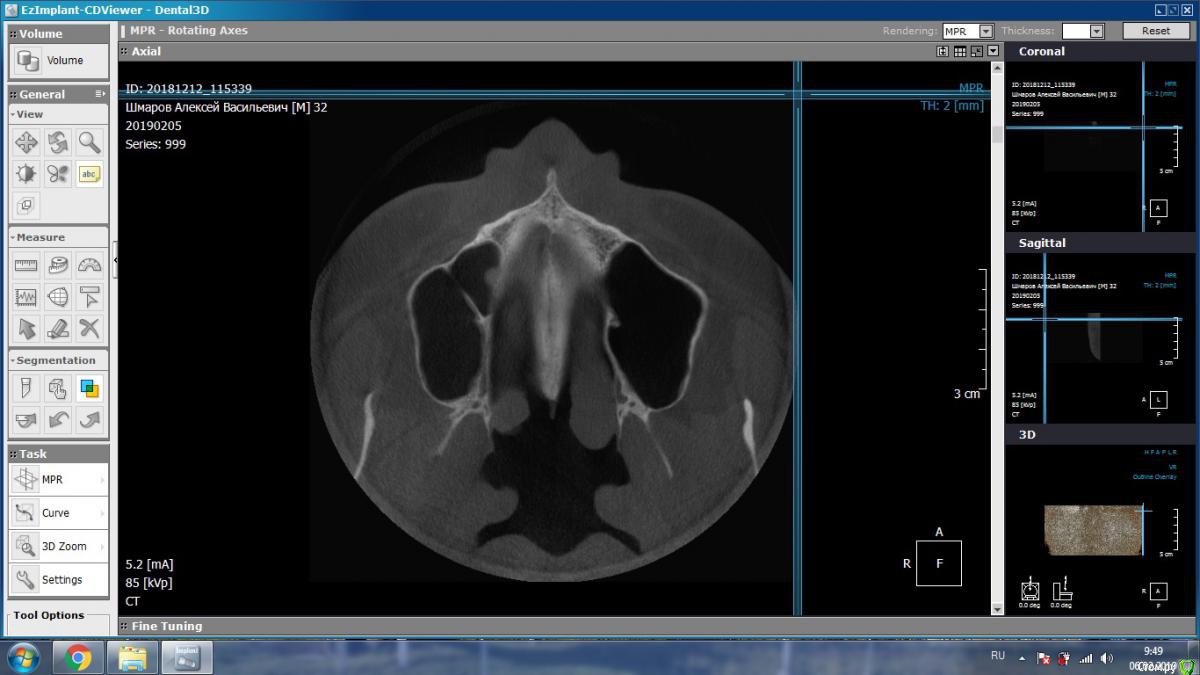

aleks.k Опубликовано 5 февраля, 2019 Автор Поделиться Опубликовано 5 февраля, 2019 Добрый день! Сделал КТ. Посмотрите пожалуйста.Есть 2 мнения очных стоматологов, пока никто из них КТ не видел, мнение на основании предыдущего панорамного снимка:1. Надо удалять 6 зуб справа2. Который и депульпировал 6 зуб сказал, что проблемы в 6 зубе нет, зуб мудрости нужно оттянуть брекетами. Размер файла 131 мб. http://fayloobmennik.cloud/7349278 Ссылка на комментарий

aleks.k Опубликовано 5 февраля, 2019 Автор Поделиться Опубликовано 5 февраля, 2019 Такие подойдут? Ссылка на комментарий

kramer Опубликовано 5 февраля, 2019 Поделиться Опубликовано 5 февраля, 2019 Судя по срезам, вероятнее причина в пульпите 7 зуба, возникшего в результате давления на него 8-ки. Ссылка на комментарий

DmitrySH Опубликовано 5 февраля, 2019 Поделиться Опубликовано 5 февраля, 2019 Такие подойдут? В Аксиальной проекции покажите еще несколько срезов Ссылка на комментарий

aleks.k Опубликовано 6 февраля, 2019 Автор Поделиться Опубликовано 6 февраля, 2019 Срезы Ссылка на комментарий

aleks.k Опубликовано 6 февраля, 2019 Автор Поделиться Опубликовано 6 февраля, 2019 Еще один срез, может быть более удачный чем первые в этой проекции Ссылка на комментарий

DmitrySH Опубликовано 6 февраля, 2019 Поделиться Опубликовано 6 февраля, 2019 Срезы Очень хорошо. Теперь как первые три, но увеличить 16 зуб. Остальные нам мало интересны, пазуха тоже Ссылка на комментарий